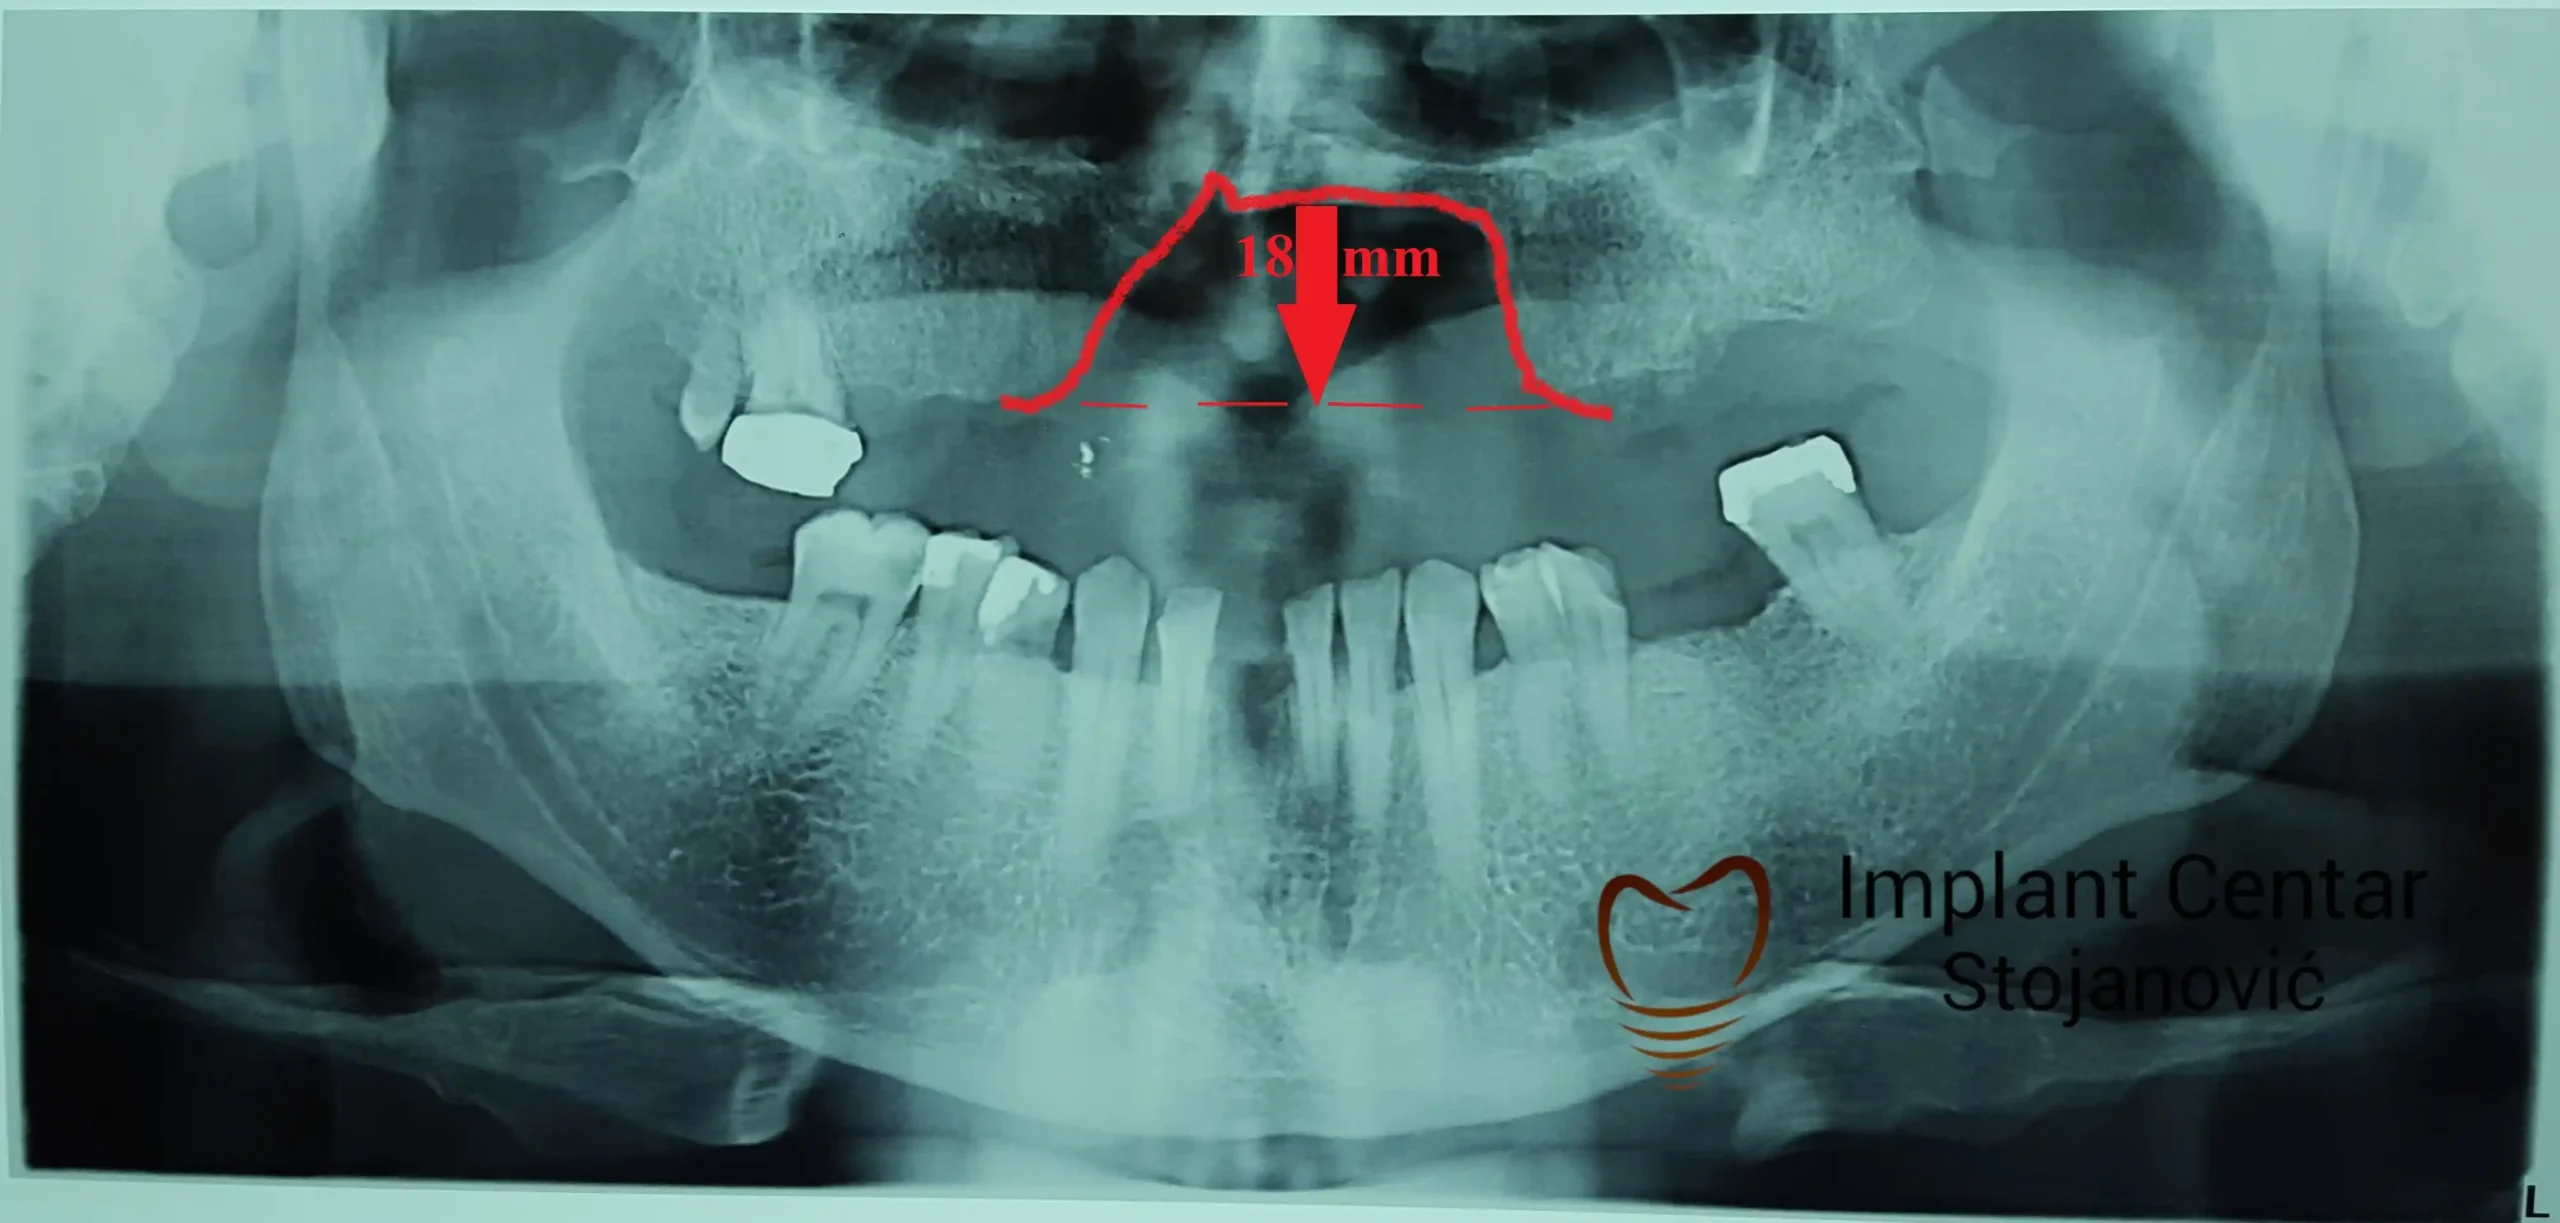

Pacijent sa rascepom usne, nepca i alveolarnog grebena uspešno je rehabilitovan fiksnim protetskim radom na implantatima. Pre dolaska u našu ordinaciju, pacijent je u gornjoj vilici nosio totalnu protezu preko preostalih zuba, dok je u donjoj vilici bio zbrinut parcijalnom mobilnom protezom. Tokom višegodišnje potrage za adekvatnim rešenjem, pacijent nije uspeo da pronađe zadovoljavajuću terapijsku opciju ni u zemlji ni u inostranstvu.

Nakon detaljnog kliničkog pregleda i analize radioloških snimaka, izrađen je sveobuhvatan plan terapije sa ciljem uklanjanja mobilnih proteza i postizanja maksimalne funkcionalne i estetske rehabilitacije. Zbog loše biološke vrednosti preostalih zuba, doneta je odluka o njihovom vađenju i ugradnji dentalnih implantata.

Poseban terapijski izazov predstavljalo je premošćavanje defekta nastalog usled rascepa, kao i ograničena količina raspoložive kosti u gornjoj vilici. Primenom većeg broja implantata i odgovarajućih procedura nadoknade kosti, postignuta je stabilna osnova za fiksni protetski rad.

Tokom perioda oseointegracije, pacijent je bio zbrinut fiksnim privremenim krunicama, čime je već pet dana nakon intervencije obezbeđena potpuna funkcionalna i estetska rehabilitacija. Nakon završetka perioda integracije implantata, izrađeni su definitivni cirkonijum-keramički mostovi na implantatima.

Pacijent je izuzetno zadovoljan postignutim rezultatom, navodeći da po prvi put jasno oseća svoje nepce tokom žvakanja, kao i da se smeje sa punim samopouzdanjem.